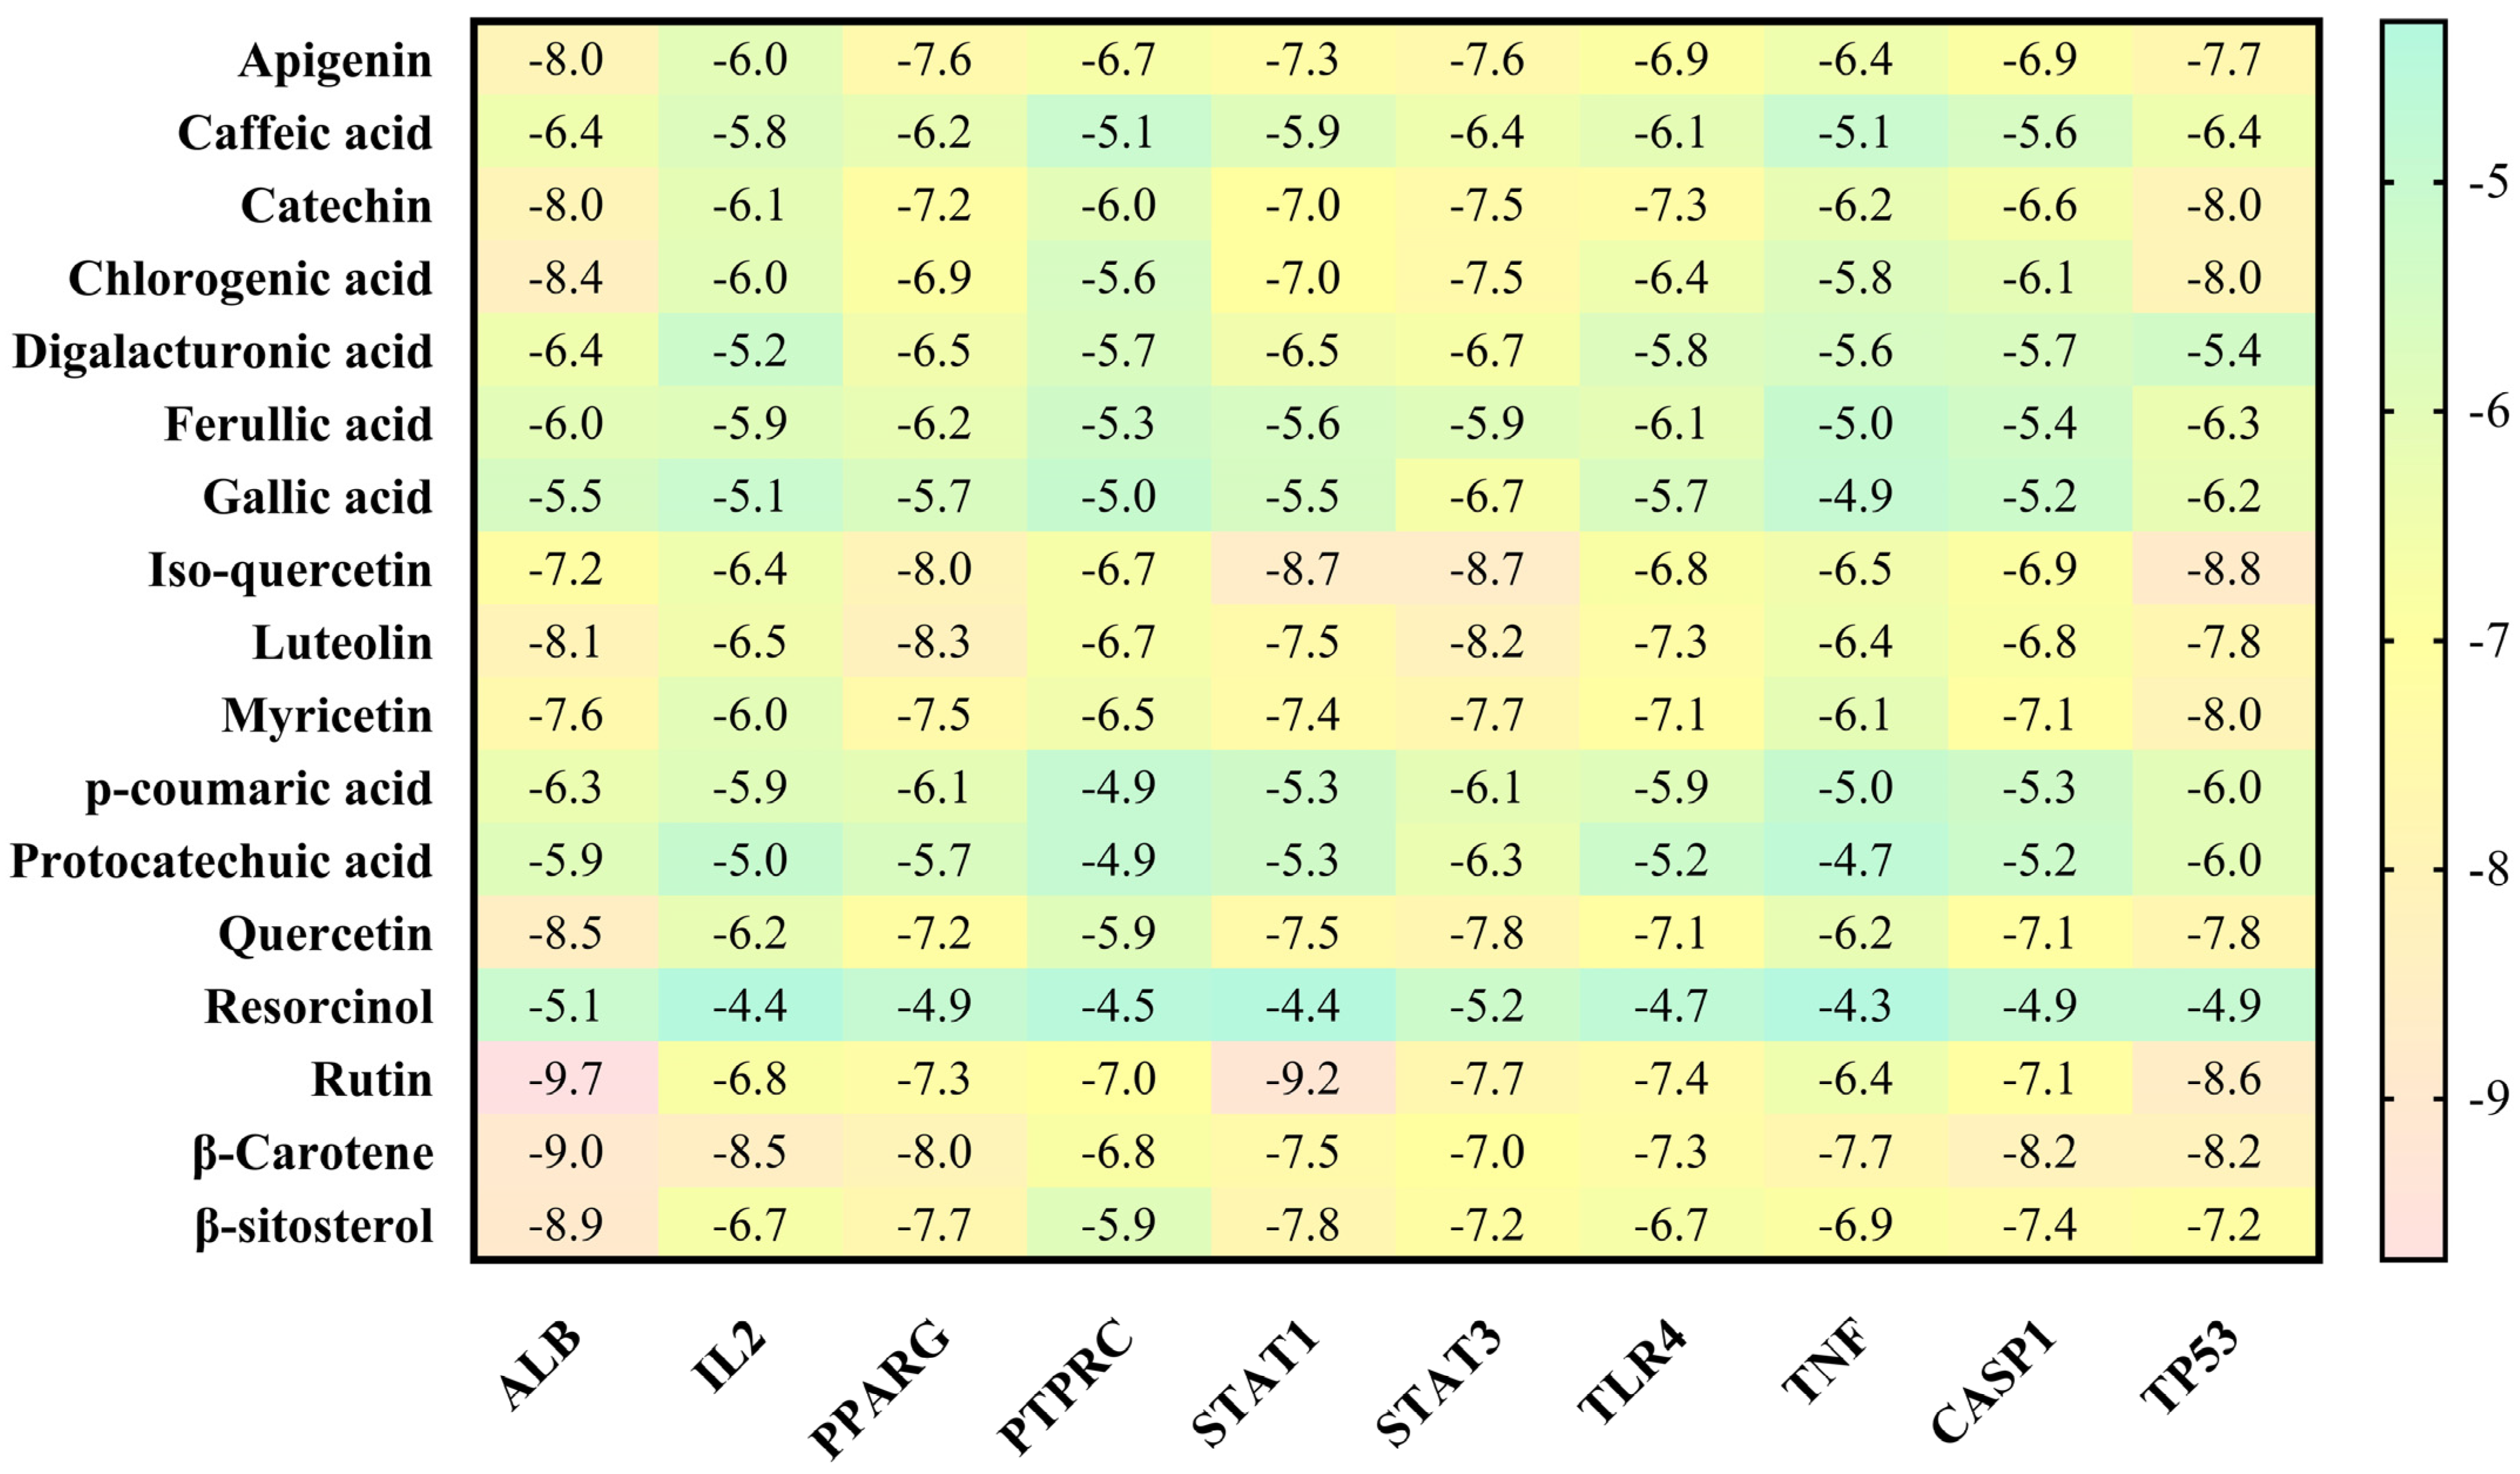

3.4. Molecular Docking Analysis

| STAT3 (signal transducer and activator of transcription 3) | Suppresses inflammation and tissue damage caused by fungal infection | STAT3 is a transcription factor that can modulate the immune response and prevent excessive inflammation and tissue damage. STAT3 can also inhibit the growth and invasion of C. albicans by regulating the expression of anti-fungal genes and enhancing the phagocytosis of fungal cells. Ajwa date extract may stimulate the release of STAT3 and enhance its anti-fungal activity. | [90,91] |

| IL-2 (interleukin-2) | Promotes T cell activation and proliferation against fungal infection | IL-2 is a cytokine that can stimulate the activation and proliferation of T cells, which are immune cells that can recognize and kill infected cells. IL-2 can also enhance the production of other cytokines that have anti-fungal effects, such as IFN-gamma and TNF-alpha. Ajwa date extract may stimulate the release of IL-2 and increase its anti-fungal function. | [69,70] |

| PTPRC (protein tyrosine phosphatase receptor type C) | Regulates T cell receptor signaling and immune response against fungal infection | PTPRC, also known as CD45, is a protein that can regulate the signaling of T cell receptor (TCR), which is a molecule that recognizes antigens presented by infected cells. PTPRC can modulate the activation and differentiation of T cells and their anti-fungal effector functions. Ajwa date extract may stimulate the release of PTPRC and improve its anti-fungal function. | [71,72] |

| STAT1 (signal transducer and activator of transcription 1) | Activates anti-fungal genes and enhances the phagocytosis of fungal cells | STAT1 is a transcription factor that can activate the expression of genes that are involved in anti-fungal responses, such as IFN-gamma, NOS2 and CXCL10. STAT1 can also enhance the phagocytosis of fungal cells by macrophages, which are immune cells that can engulf and destroy foreign particles. Ajwa date extract may stimulate the release of STAT1 and increase its anti-fungal function. | [90,92] |

| CASP1 (caspase-1) | Induces the pyroptosis (inflammatory cell death) of infected cells and prevents fungal dissemination | CASP1 is a protein that can trigger pyroptosis, which is a process of inflammatory cell death, in the response to fungal infection. Pyroptosis can help eliminate infected cells and prevent the spread of fungal pathogens. Pyroptosis can also release cytokines, such as IL-1beta and IL-18, that have anti-fungal effects. Ajwa date extract may stimulate the release of CASP1 and increase its pyroptotic function. | [74] |

| ALB (albumin) | Binds to fungal toxins and neutralizes their effects | ALB is a protein that can bind to various substances in the blood, including fungal toxins such as gliotoxin and fumagillin. ALB can neutralize the effects of these toxins on immune cells and tissues. Ajwa date extract may stimulate the release of ALB and enhance its anti-toxin activity. | [75] |

| TP53 (tumor protein p53) | Induces the apoptosis (cell death) of infected cells and prevents fungal dissemination | TP53 is a protein that can trigger apoptosis, which is a process of programmed cell death, in response to DNA damage or stress. Apoptosis can help eliminate infected cells and prevent the spread of fungal pathogens. Ajwa date extract may stimulate the release of TP53 and increase its apoptotic function. | [93] |

| TLR4 (Toll-like receptor 4) | Recognizes fungal components and activates the inflammatory response against fungal infection | TLR4 is a protein that can recognize fungal components such as lipopolysaccharide and beta-glucan. TLR4 can activate the inflammatory response against fungal infection by inducing the expression of cytokines such as TNF-alpha, IL-1beta, IL-6, IL-12 and IL-23. Ajwa date extract may stimulate the release of TLR4 and increase its anti-fungal function. | [77] |

| TNF (tumor necrosis factor) | Induces inflammation and cell death against fungal infection | TNF is a cytokine that can induce inflammation and cell death against fungal infection by activating the expression of genes such as NOS2, CXCL10 and ICAM1. TNF can also enhance the phagocytosis of fungal cells by macrophages and neutrophils. Ajwa date extract may stimulate the release of TNF and increase its anti-fungal function. | [78] |

| PPARG (peroxisome proliferator-activated receptor gamma) | Inhibits fungal growth and biofilm formation | PPARG is a protein that can inhibit the growth and biofilm formation of C. albicans by regulating the expression of genes such as EFG1, NRG1 and HWP1. PPARG can also modulate the immune response and inflammation against fungal infection by influencing the production of cytokines such as IL-10, IL-17 and TGF-beta. Ajwa date extract may stimulate the release of PPARG and increase its anti-fungal function. | [79] |